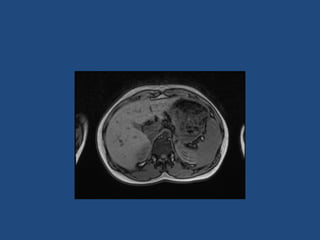

Imaging

>6cm high suspicion of malignancy

3-6cm repeat imaging in 3-6M

Delayed washout on contrast is suggestive

most are often inhomogeneous, irregular

margins

• Look for invasion of IVC

• Always do CAP and consider bone scan and

pet if in doubt

• Don’t ever biopsy (tumour spill)